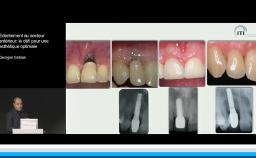

La présentation s’attache à détailler en quoi l’implantation en zone esthétique constitue un challenge lorsqu’il s’agit de réhabiliter la fonction sans oublier de rétablir l’esthétique. A travers quelques cas cliniques, le Dr Eycken s’appuie sur la classification SAC de l’ITI pour évaluer la complexité du cas et y apporter la solution thérapeutique adaptée. Il revient également sur l’importance du positionnement de l’implant dans les 3 sens de l’espace et sur la qualité des tissus mous environnants.

• de cerner les situations cliniques à risque dans le cadre de la pose d’un implant au maxillaire antérieur

• de positionner un implant correctement dans les 3 plans de l’espace